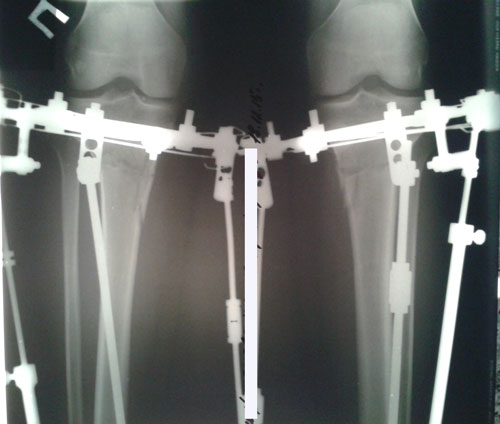

Дата операции 03.12.2015г.

У пациентки начальная стадия артроза, остеопороз, протрузия диска L5- S1